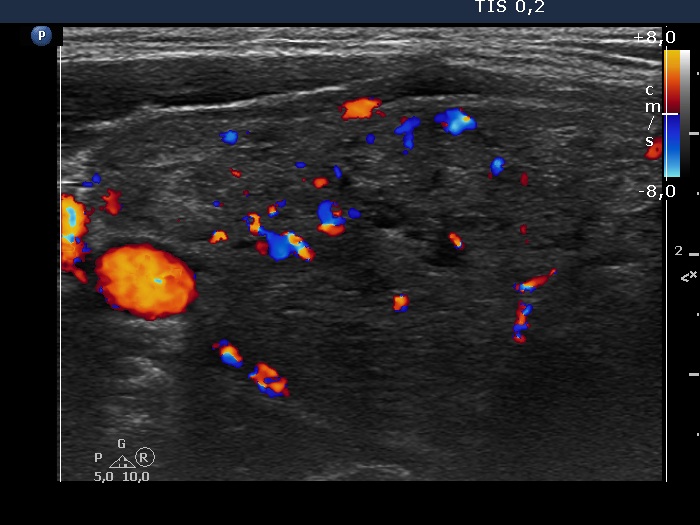

Ultrasonography. The thyroid was greatly enlarged and was composed of numerous nodules. The non-nodular part appeared as echonormal islets within the thyroid. The nodules varied in echogenicity which ranged from moderately hypoechogenic to hyperechogenic. Most nodules had cystic areas, as well. There was no nodule of oncological significance.